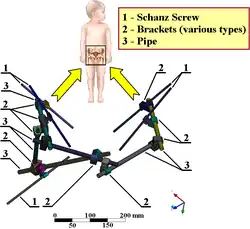

Zevní fixace zlomeniny pelvisu

Zevní fixace zlomeniny pelvisu -